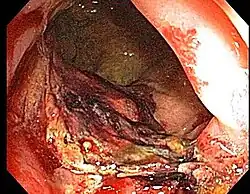

- Etiology: obliterative endarteritis and chronic mucosal ischemia, leading to progressive epithelial atrophy and fibrosis. Ultimately, development of a chronically ischemic intestine prone to fibrosis and bleeding

- Symptoms: diarrhea, obstructed defecation (if strictures), bleeding, rectal pain, rectal urgency, and fecal incontinence. Rarely fistulas, SBO

- Diagnosis: colonoscopy, barium studies if suspecting strictures and fistulas

- Formaldehyde - induction of coagulative necrosis; beneficial for bleeding

- Endoscopy (Argon plasma coagulation) - benefit for bleeding